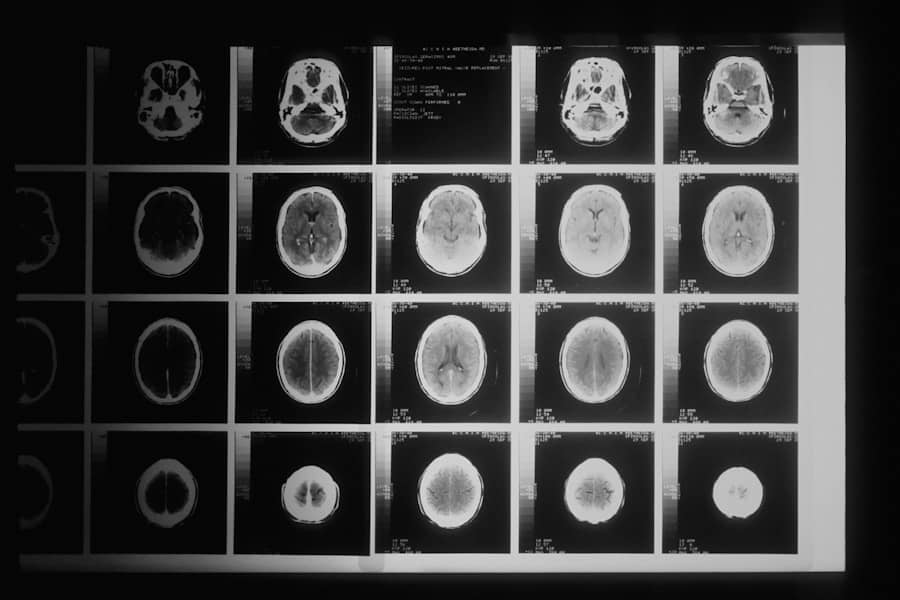

Dijagnoza tumora obično podrazumijeva biopsiju i patohistološki pregled, uz dodatne pretrage kao što su snimanja i analize krvi. Kada je dijagnostikovan maligni tumor, onkolog određuje stadijum i plan liječenja. Benigni tumor često se prati redovno, a uklanjanje se preporučuje samo po potrebi. Pravovremena dijagnoza i adekvatno liječenje su presudni za ishod.